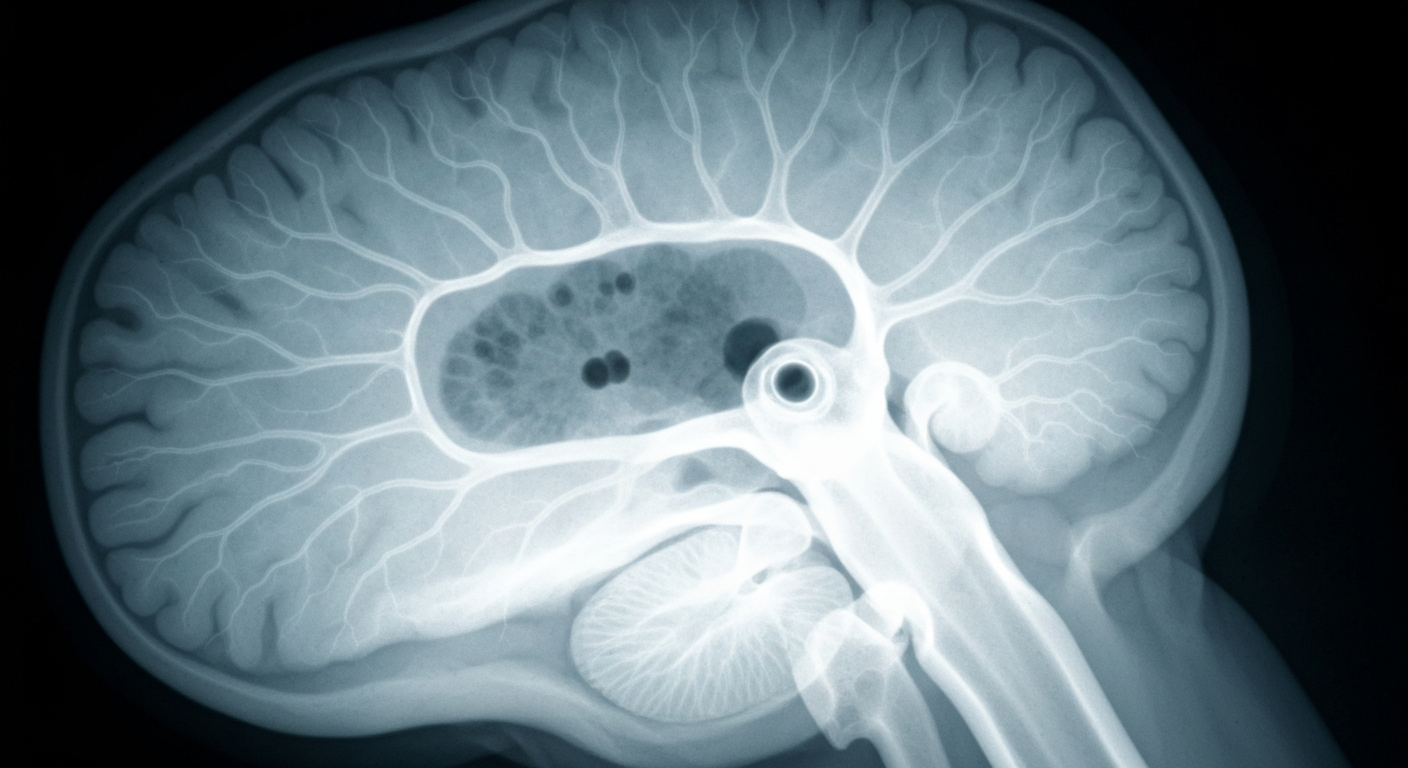

An X-ray view into the delicate workings of the brain's blood vessels, where exposure to a common sweetener may disrupt normal function.Boulder TodayResearchers at the University of Colorado Boulder have found that erythritol, a common sugar alcohol used as a sweetener in protein bars, zero-sugar drinks, and other foods, may increase the risk of stroke and blood clots. Their study showed that exposure to erythritol led to changes in human brain blood vessel cells, including reduced production of nitric oxide to relax blood vessels and increased production of a compound that constricts them. The researchers also found the erythritol blunted the cells' ability to break down blood clots.